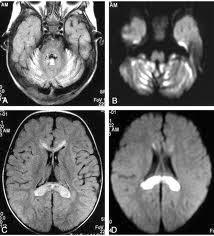

enzyme action in refined fibroblasts is the analytic test.Imaging Studies Brain

MRI may prove white matter irregularities, chiefly in the periventricular area.